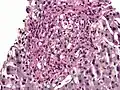

Histoplasma. PAS diastase stain.